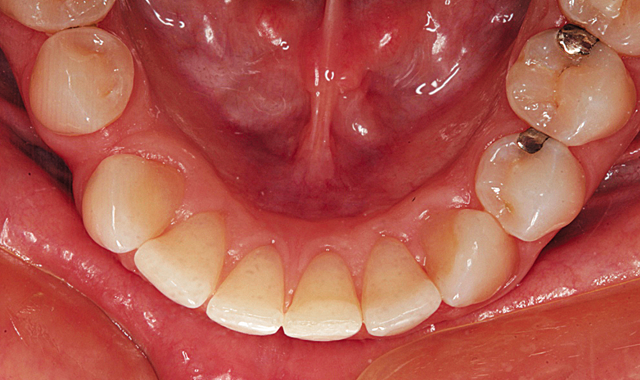

In the incisal view of the maxillary teeth, you can see that the mal-alignment was almost completely confined to the left central and lateral incisor and canine (Fig. 3). The mandibular anterior had the opposite problem with most of the crowding being in the area of the right central, lateral and canine as can be seen in Figure 4. Mary decided that she wanted to have Inman Aligners to straighten her anterior teeth.

Fig. 3

Fig. 4